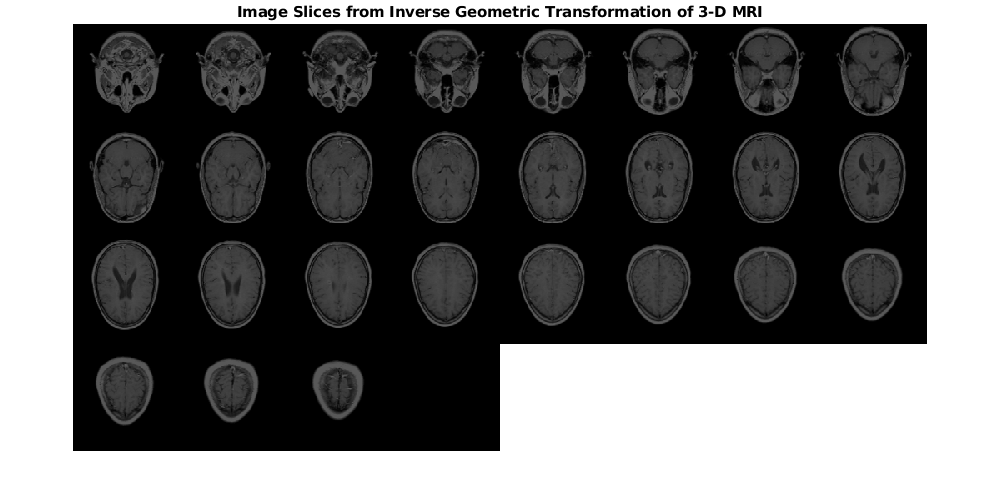

Используйте imwarp применять обратное геометрическое преобразование к объему входа MRI.

[mriVolumeTransformed] = imwarp(mriVolume,tform,'nearest','SmoothEdges',true);

Отобразите фрагменты изображения от преобразованного объема MRI как монтаж. Срезы преобразованного изображения являются отражением входных фрагментов изображения через ось X.

montage(mriVolumeTransformed,'Size',[4 8],'BackgroundColor','w')

title('Image Slices from Inverse Geometric Transformation of 3-D MRI','FontSize',14)